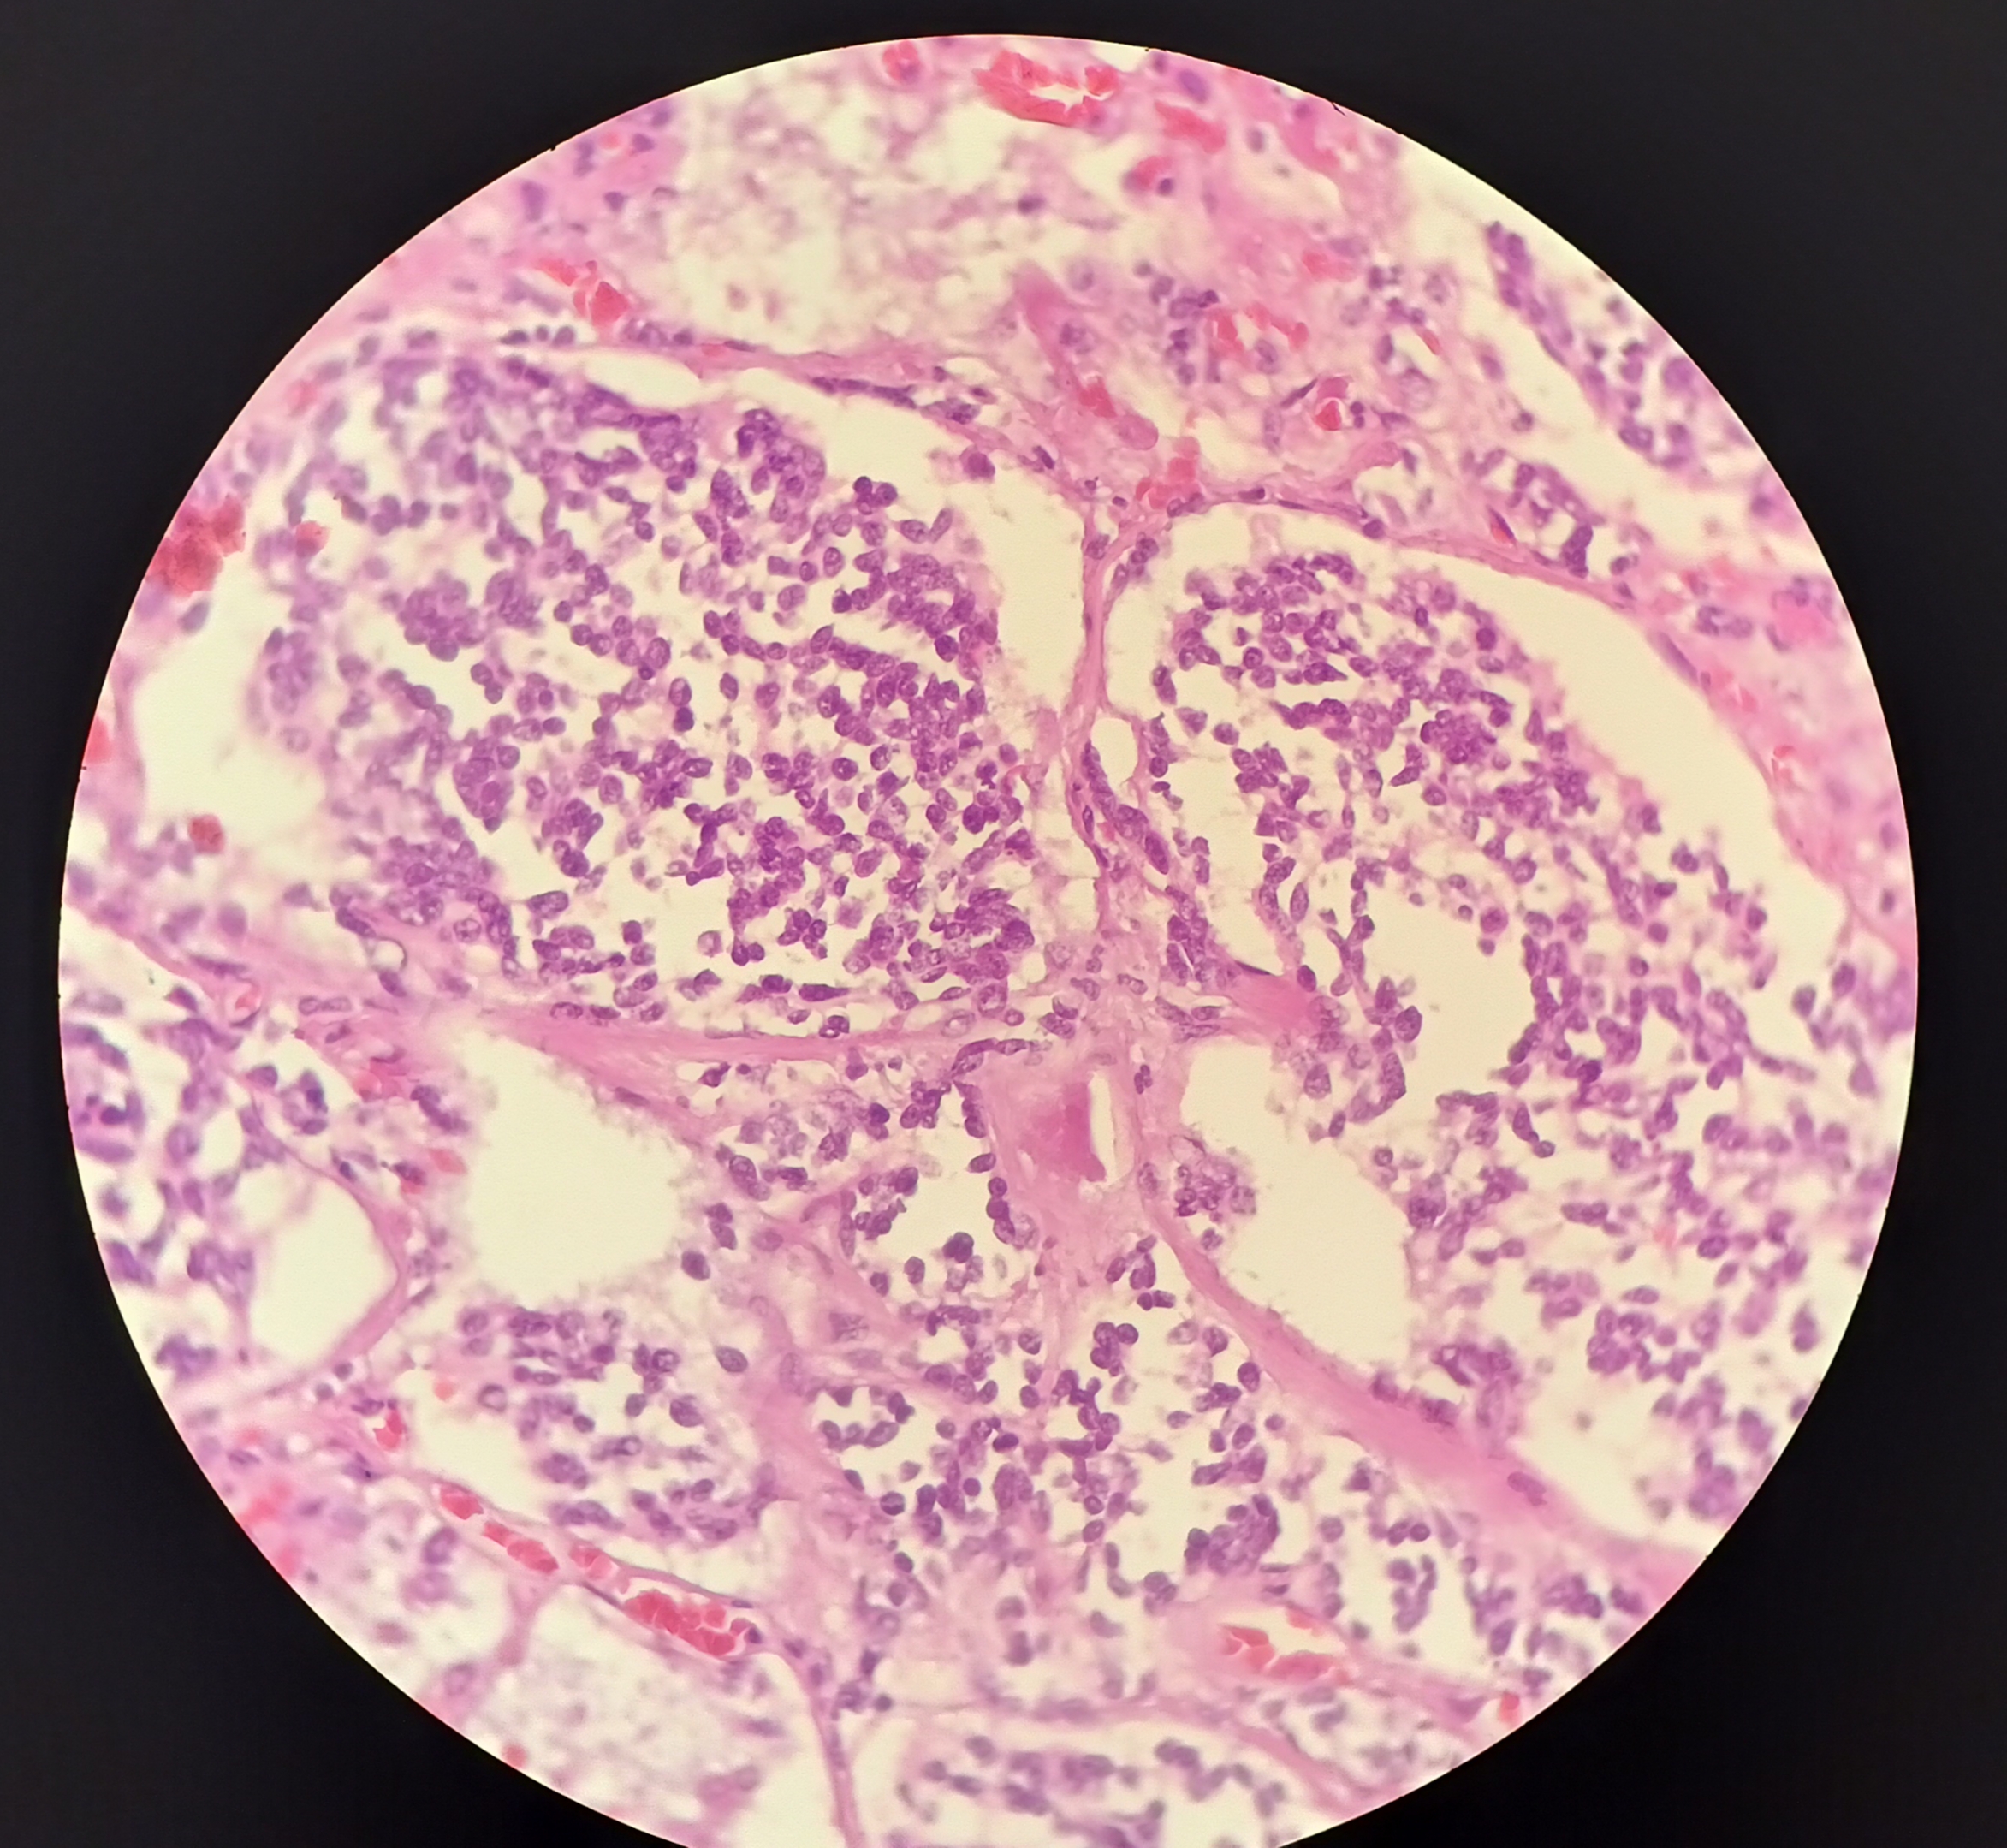

Фотографии опухоли медуллярной аденокарциномы

Раздел: Снимки-откровения